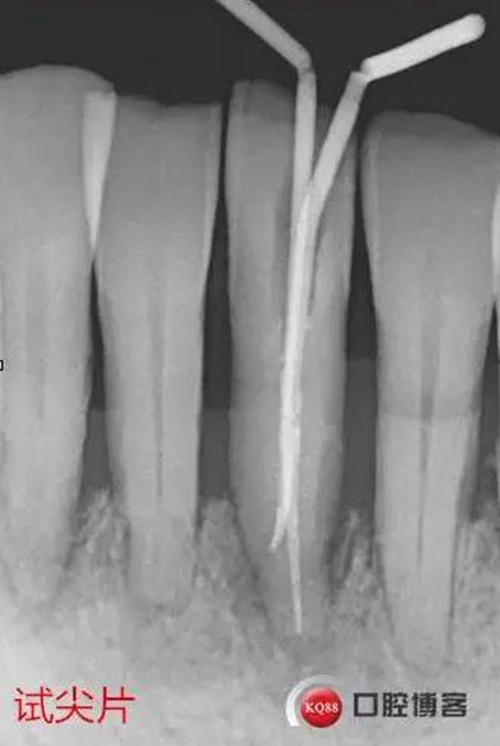

處理:上橡皮障,31開(kāi)髓,測(cè)工作長(zhǎng)度17mm,含氯沖洗液沖洗,機(jī)擴(kuò)至04錐度30#,超聲蕩洗,一次性根充。33-43牙齒鄰接處super bond粘結(jié)固位,行松牙固定。調(diào)合。拍根充術(shù)后片,未達(dá)根尖,懷疑遺漏根管,去除根充物后,繼續(xù)探查根管,找到舌側(cè)根管,測(cè)長(zhǎng)度20mm,時(shí)間原因,未行擴(kuò)根,氫氧化鈣暫封。

圖省事,沒(méi)有拍術(shù)中試尖片,導(dǎo)致術(shù)后重新去除根充物,再次探查,耽誤時(shí)間。

事后再次查看術(shù)前片,可以看到兩個(gè)根管影像,忽略了。

處理:31去暫封,手用銼疏通根管,沖洗,機(jī)擴(kuò)至04錐度30#,超聲蕩洗,封維塔,拍片。

處理:31去暫封,疏通根管,沖洗,試尖,拍片,根充,拍片,恰填,根尖孔外無(wú)多余藥物滲出。樹(shù)脂充填開(kāi)髓孔。33-43樹(shù)脂纖維帶固定,調(diào)合拋光。